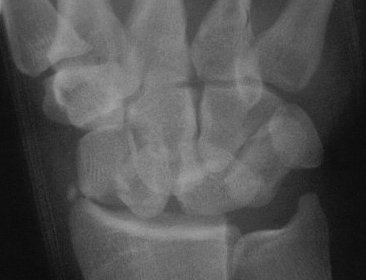

1. Nondisplaced fracture in a surgeon who declined continuous immobilization.

One week after screw stabilization using a limited dorsal approach, he was back operating, but splinted when not scrubbed. These films are one month post op: no visible fracture.